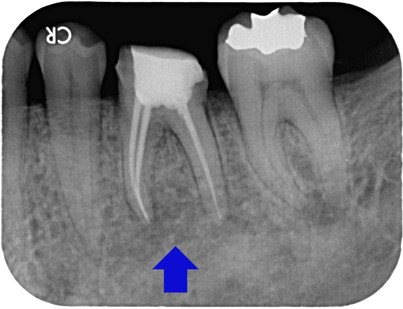

治療前

左下の奥歯に詰め物が入っていますが、歯の中にある神経がばい菌に感染してしまい痛んでいる状態でした。 |

詰め物を外し、壊死した神経を取り除き根っこを傷めないように丁寧に根管治療を行いました。 |